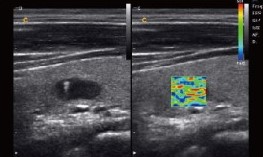

Опции:

Эластография позволяет оценивать плотность и эластичность тканей в реальном времени, что особенно важно при исследовании печени и молочных желез.